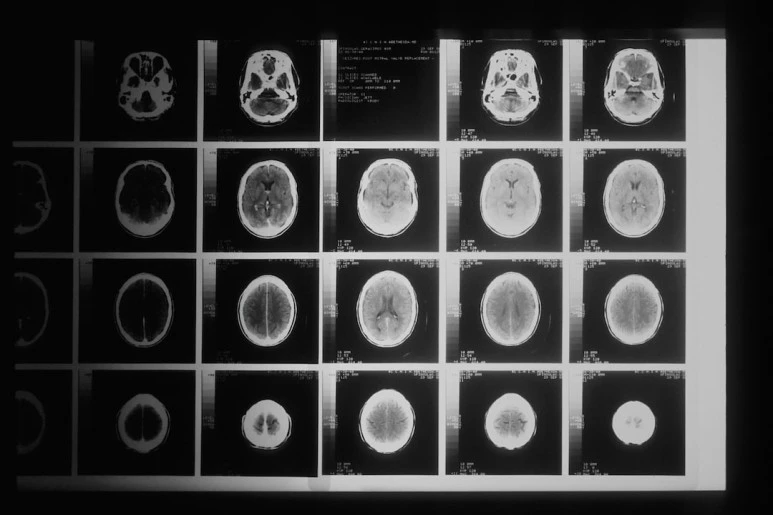

photo-1631563019676-dade0dbdb8fc.jpg?type=w773 © nci, 출처 Unsplash

뇌출혈 뇌경색 수술 후유증으로 물덩어리가 생겼다는데 그것 때문인지 영 할머니의 고개 젓음이 예사롭지 않다. 그래서 말을 잃어버린 건지... 그 누구도 할머니의 상태에 정확하게 판단 내리지 못해 더 답답할 따름이다. 이 모든 건 할머니가 가장 잘 알거라 생각이 들면서도 어쩌면 현재도 모르고 가장 답답할 사람. 그게 할머니일지 모른다는 생각에 안타까울 따름이다.